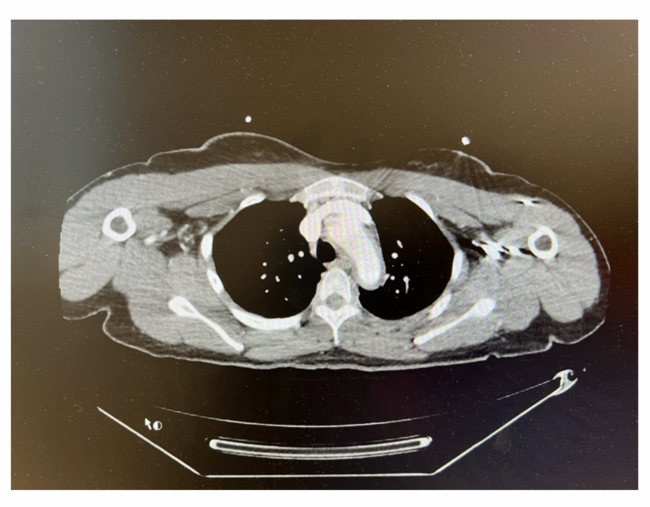

A 28-year-old right-handed woman with no significant medical history presented with aphasia and right arm weakness of 3-day duration. Noncontrast head computed tomography (CT) showed a subacute left parietal infarct without hemorrhage. The aortic wall had a 0.4-cm thickening. Figure 1 depicts the underlying inflammatory condition/edema.

As shown in Figure 2, a neck CT with contrast showed abnormal wall thickening and hyperenhancement of the aortic arch, left common carotid artery (CCA), and right carotid bifurcation. Vertebral arteries were patent and the Circle of Willis intact. The left CCA was totally occluded, as was the left internal carotid artery (ICA) through its distal cervical and proximal intracranial segments, with eventual reconstitution at the terminus and paraclinoid segments. The external carotid artery (ECA) was also occluded, so the procedure was stopped before the ECA, which would usually have been involved in cases of no occlusion. High-grade stenosis of the origin of the right ICA was noted. Of note, a Streptococcus A rapid test was positive. Inflammatory markers were marginally elevated. The patient was transferred to our tertiary medical center for further management.